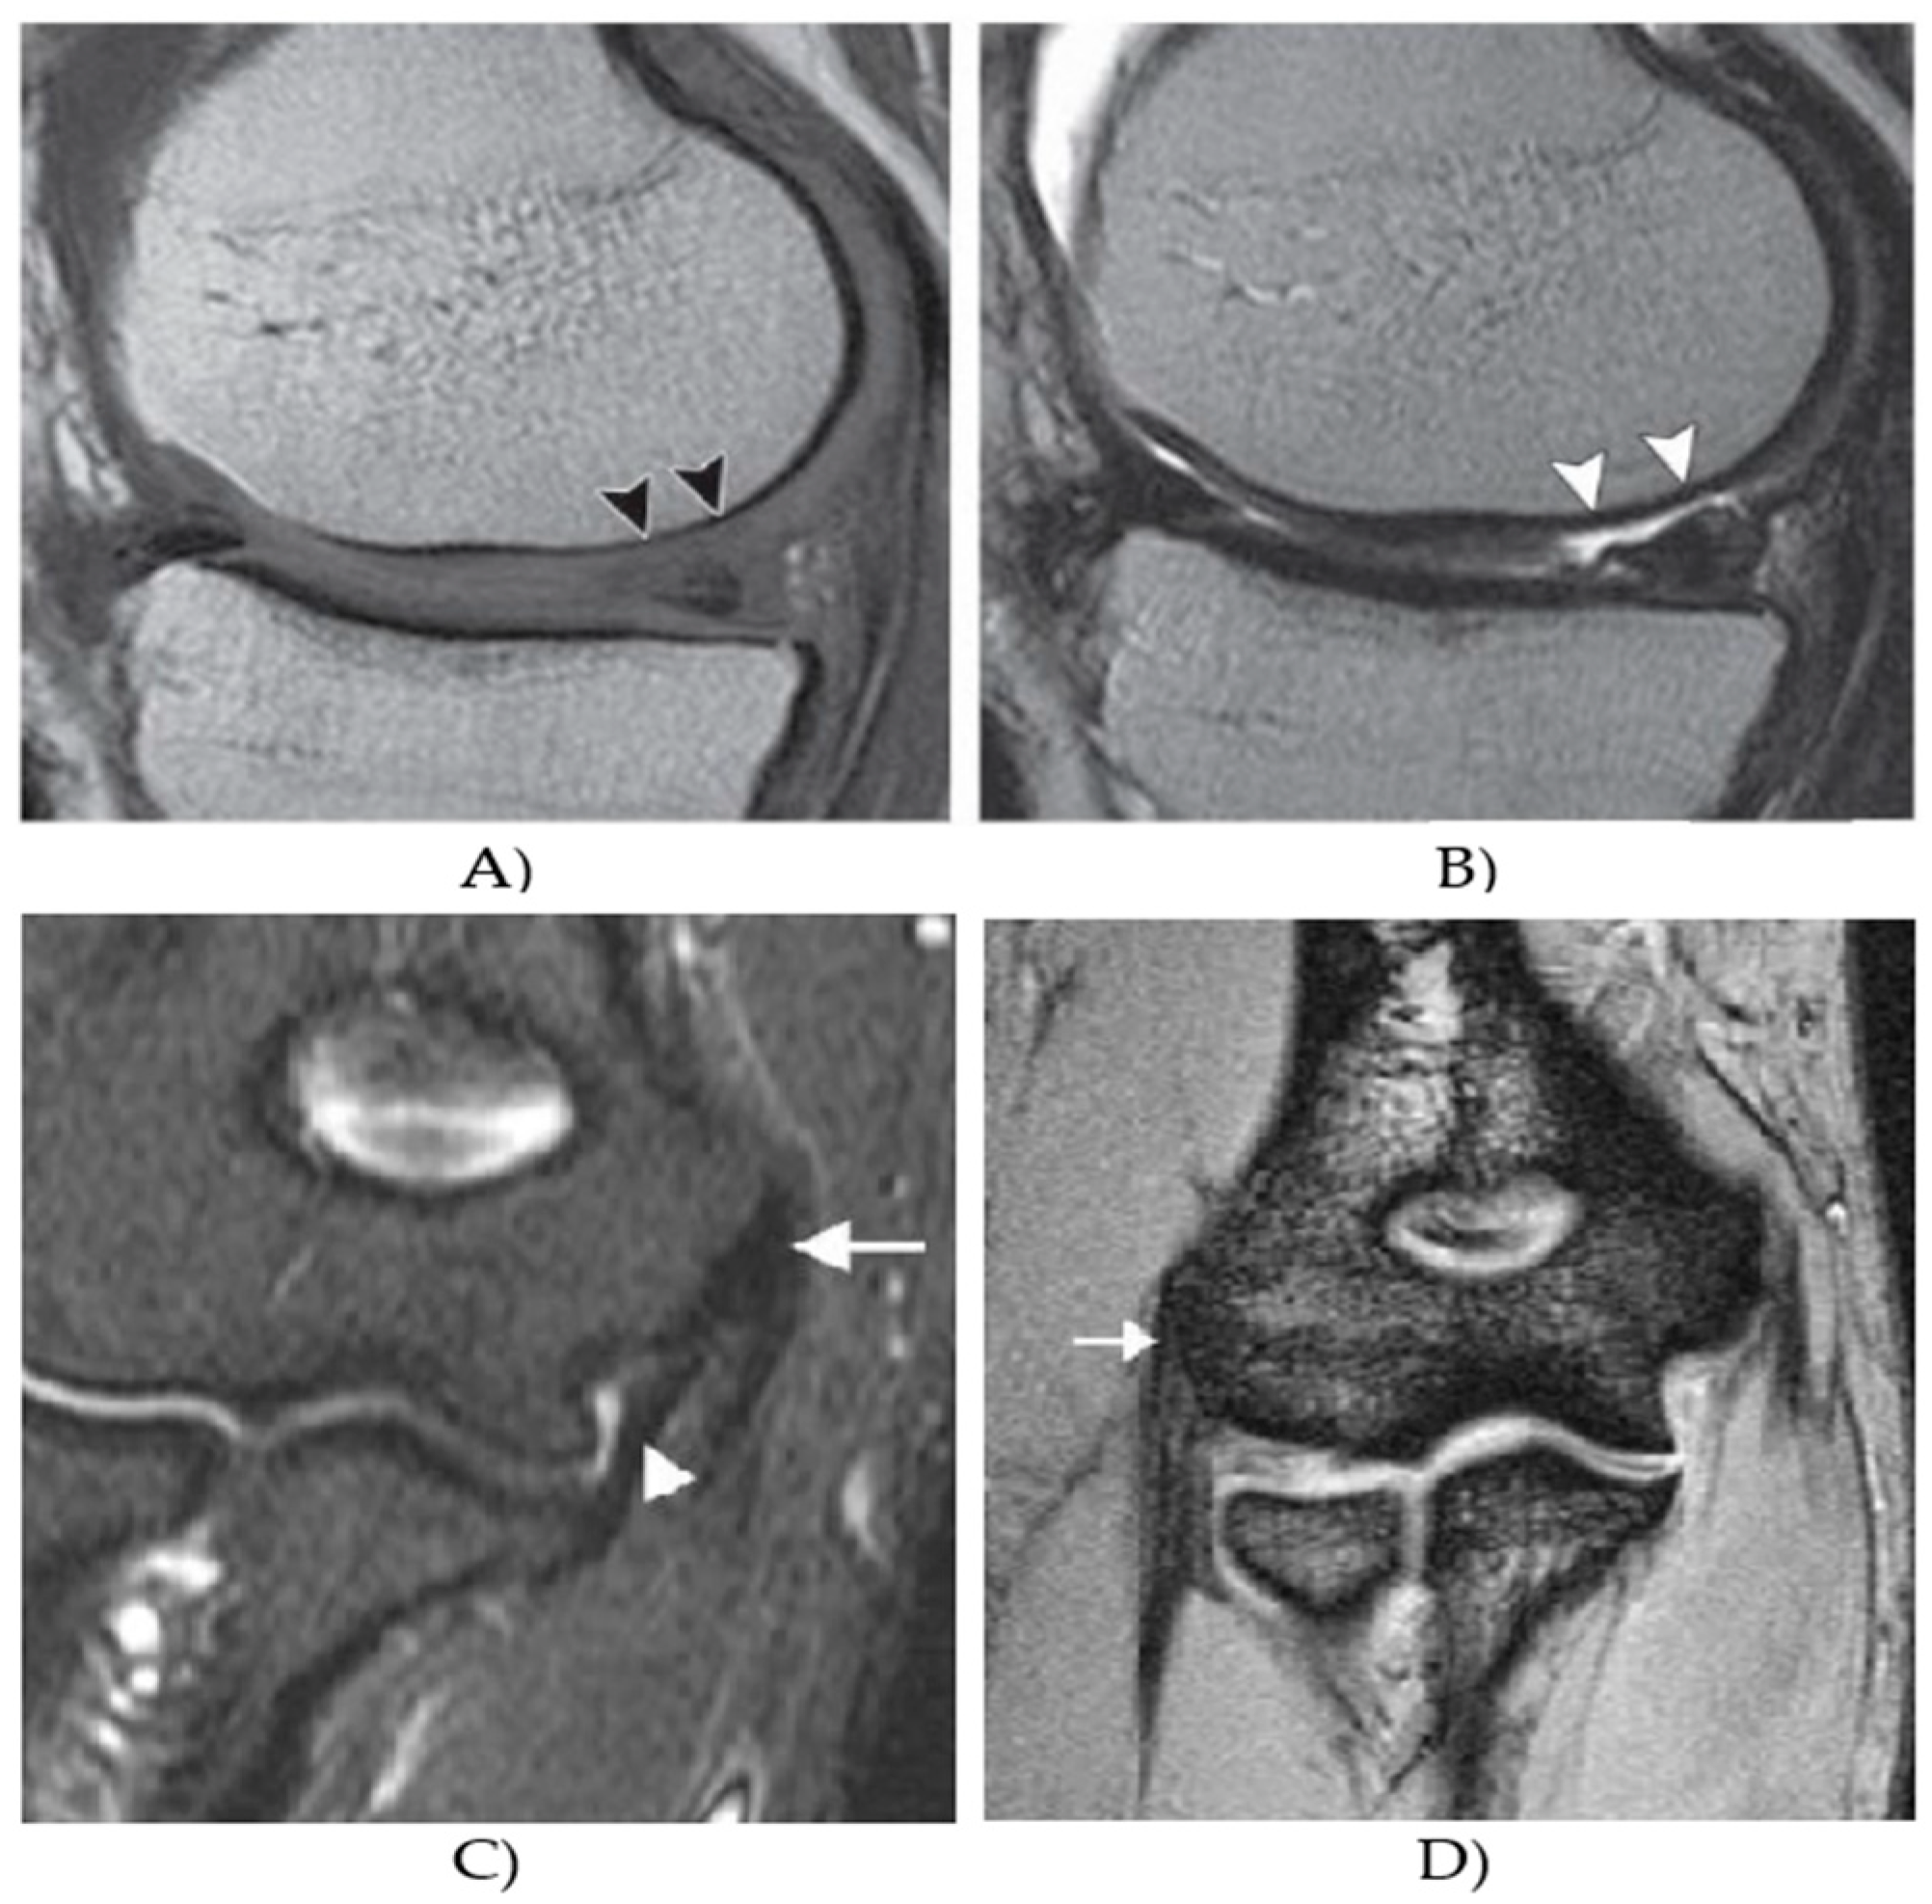

| Findings | Early cartilage osteoarthritis | Cartilage lesions | Healthy elbow muscle |